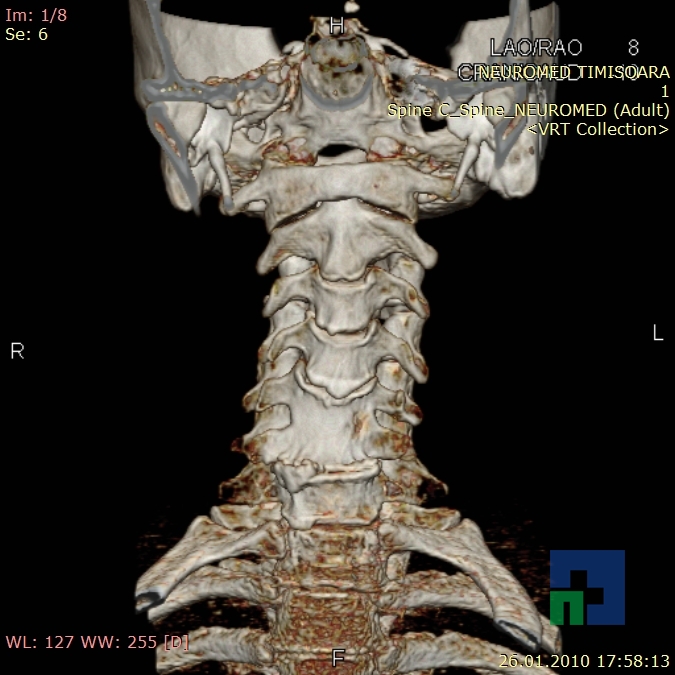

În cazul traumatismelor cranio-cerebrale:

- Diagnosticul traumatismelor de bază de craniu

- Diagnosticul fracturilor:

- Unice

- Multiple

- Cu înfundare

- Complexe cranio-sinusale

- Complexe cranio-etmoidale

- Complexe cranio-orbitare

- Complexe cranio-faciale